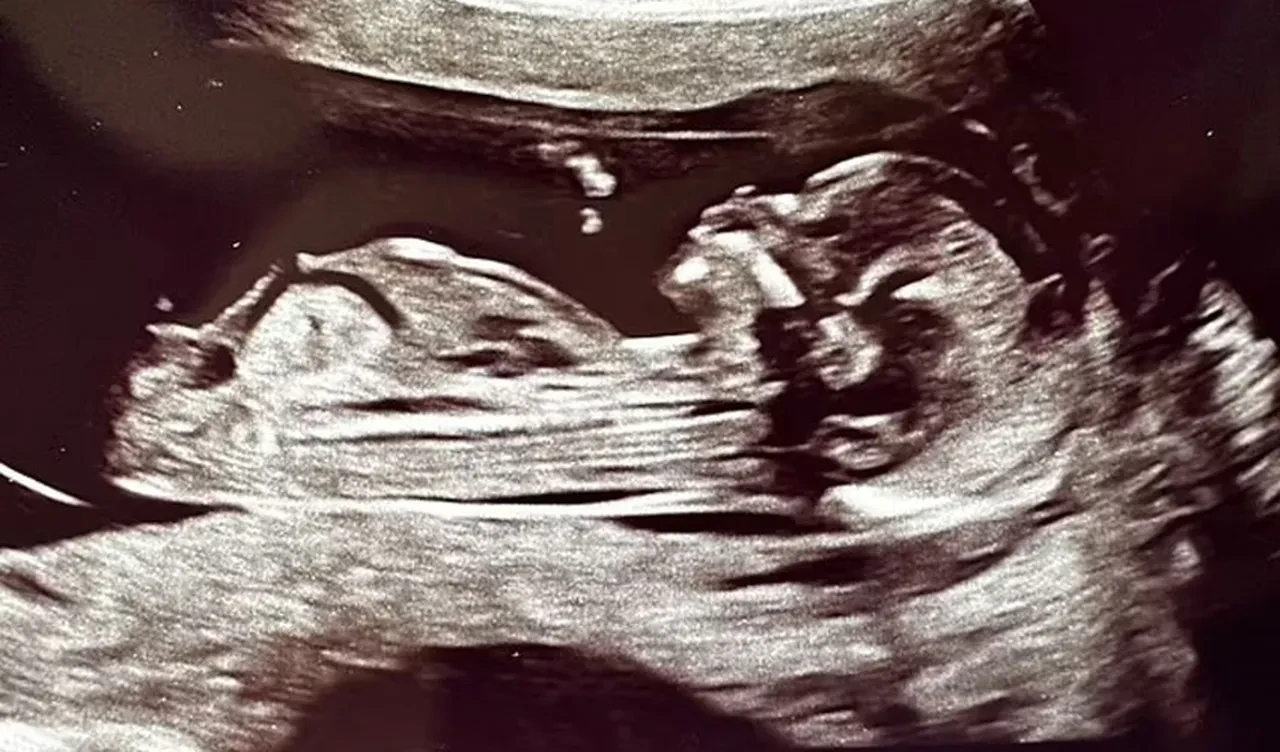

Lucy hamileliğinin 20. haftasında ameliyata alındı ve rahmi içindeki bebekle beraber vücudundan çıkarıldı. Ekip, oldukça dikkatli bir şekilde kanserli hücreleri temizledi. Bu esnada rahim, uterin arter yoluyla bebeğe kan ve oksijen sağlamaya devam etti. İki saat süren ameliyat boyunca rahim dışarıda tutulurken steril tuzlu su torbaları sayesinde uygun sıcaklık da sağlandı. Ayrıca bebeğin kalp atışı sürekli olarak kontrol edildi.

Lucy'nin ameliyatı oldukça başarılı geçti, rahim tekrar vücuda yerleştirildi ve hamileliğin devamı sağlandı. Bebek Rafferty, ocak ayında sağlıklı bir şekilde dünyaya gözlerini açtı.